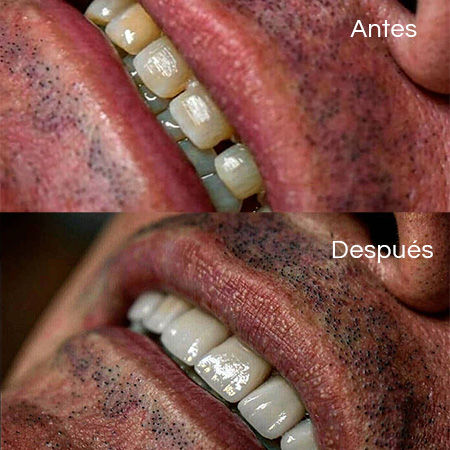

Before and After Gallery